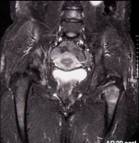

Metastatic deposits

Breast cancer and hip pain